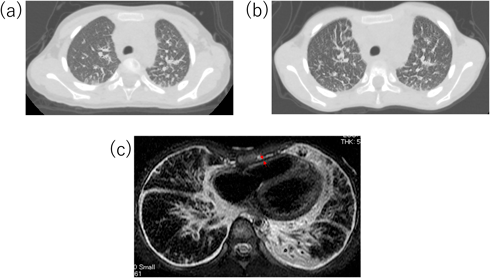

しかし,治療終了後も胸部X線で肺間質陰影の増強が改善せず,発症から3カ月後の胸部単純computed tomography(CT)検査で肺小葉間隔壁の肥厚を認めた(Fig. 2a).本人の自覚症状は特になく,肺線維化マーカーの上昇を認めず,心嚢液再貯留も認めなかったため,外来経過観察を継続した.外来経過観察中,下腿浮腫や肝腫大など右心不全症状は認めず,心臓超音波検査も繰り返し行われたが,心機能は良好で心嚢液の再貯留もなく,拡張障害も明らかでなかった.しかし,胸部X線所見は改善せず,発症後5年頃から徐々に易疲労感を認めるようになったため8歳時に胸部単純CT検査を再検したところ,肺小葉間隔壁の肥厚は悪化していた(Fig. 2b).心筋症の鑑別に心臓MRIを撮像し,心筋の肥厚や菲薄化は認めず遅延造影も陰性で心筋症は否定的であったが,心膜肥厚を認め(Fig. 2c),収縮性心膜炎が鑑別に挙がった.その精査のため,また心筋症の鑑別のため,9歳時に心臓カテーテル検査を行った.その時の圧データをTable 1に,右室圧曲線をFig. 3に示す.右室拡張末期圧の上昇を認めず,右室圧波形もdip and plateau型を示しておらず,収縮性心膜炎も否定的な所見であった.心筋生検も行ったが,錯綜配列などは認めず心筋症も否定された.

収縮性心膜炎は,心膜の肥厚が原因とされ,成人では4 mm以上の壁厚が肥厚と判定される13).心臓超音波検査における拡張障害や,心臓カテーテル検査における心内圧曲線でdip and plateauが特徴的とされる.dip and plateau波形は,ゼロ以下の拡張期下降から急峻な立ち上がりで拡張期plateauに続き,拡張期plateau圧は収縮期の3分の1を超えるとされている14).本症例は心膜肥厚を疑う所見を認め(Fig. 2),心臓超音波検査で拡張障害は明らかでなかったが,その時点ではGLA/GSD病は鑑別に挙がっておらず,病歴からも収縮性心膜炎の可能性が高いと考えられたため,心臓カテーテル検査を行った.しかし,心臓カテーテル検査でもdip and plateau型の心内圧曲線は認めず(Fig. 3),収縮性心膜炎は否定的であり,心筋生検も行ったが心筋症も否定された.